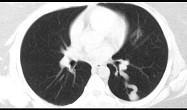

问题 30岁,偶有干咳,结合影像图像,选择最可能的诊断 ( )

选项 A.左下肺感染 B.左下肺结核 C.左下肺错构瘤 D.左下肺炎性假瘤 E.左下肺动静脉畸形

答案 E